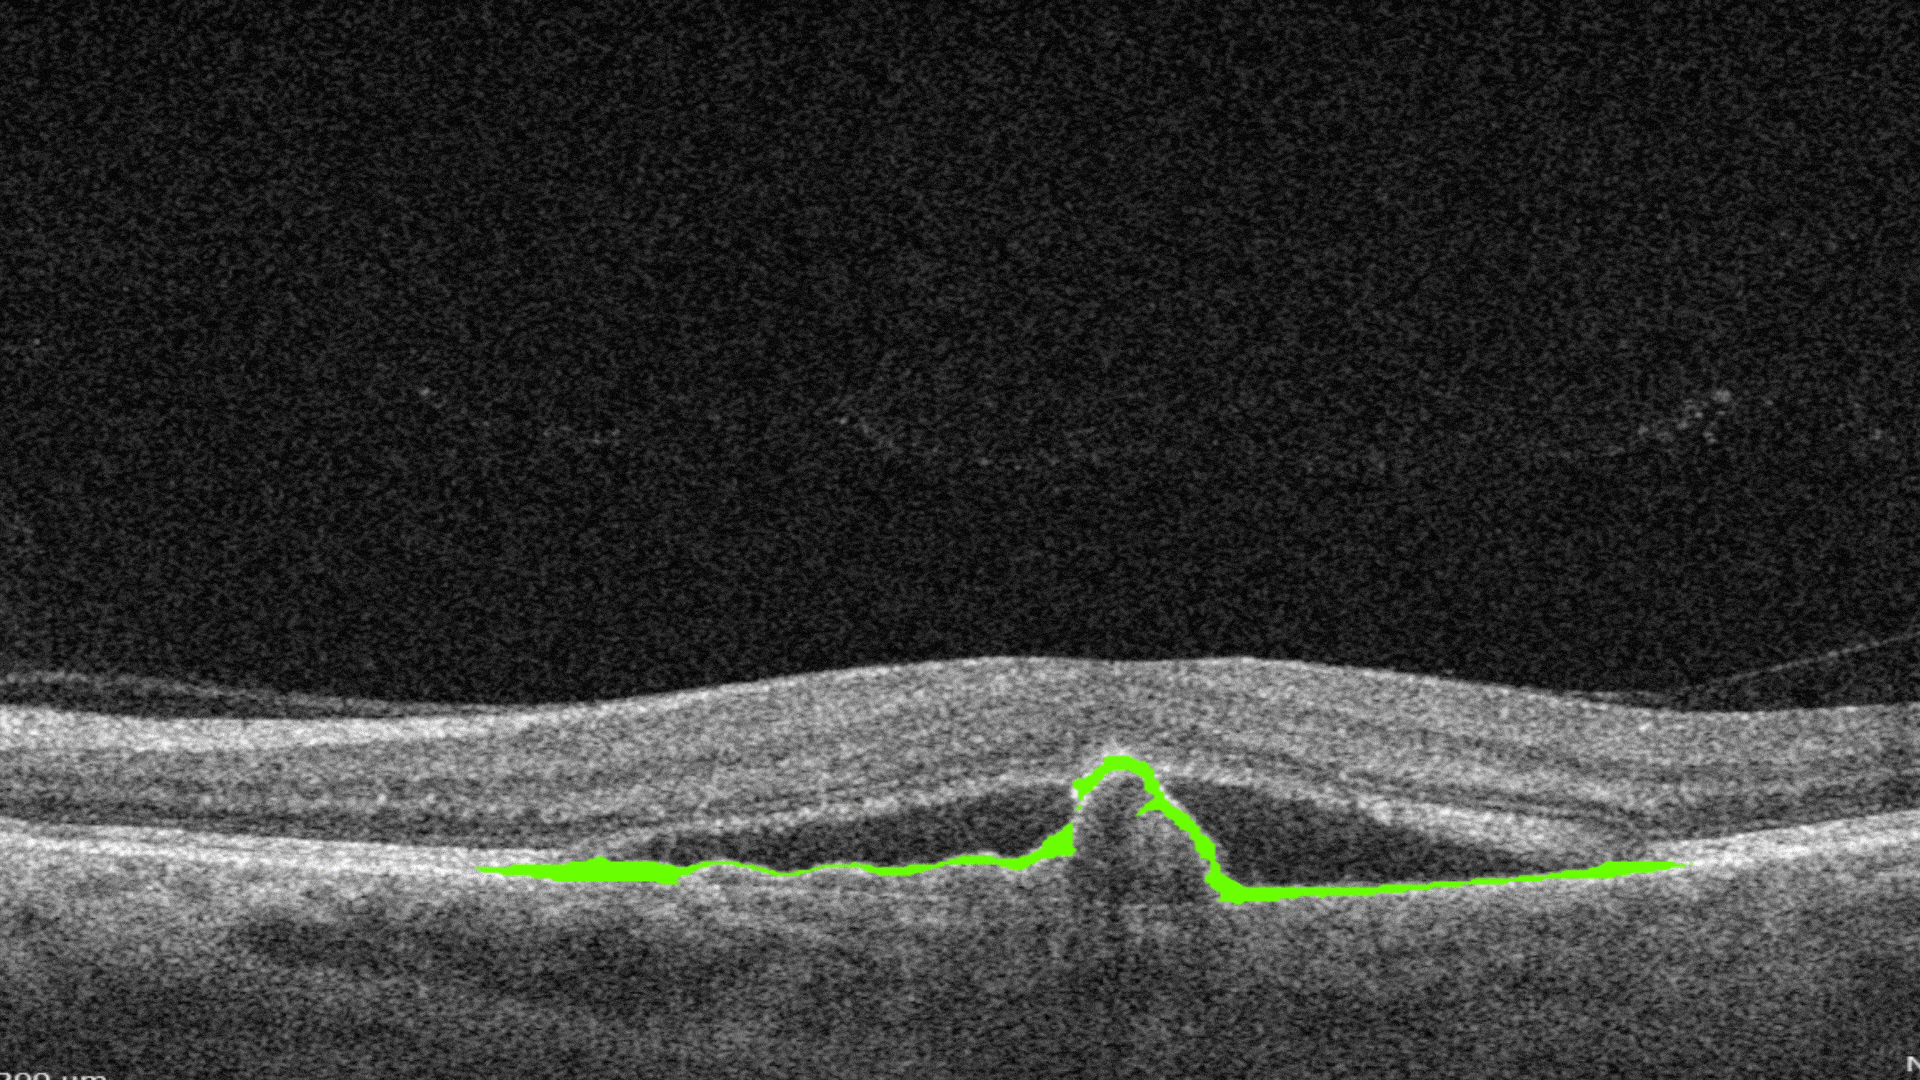

Ellipsoid zone disruption is the changes in the photoreceptor layer can be identified as a disruption or defect in the ellipsoid zone (EZ).

-

RPE Disruption is the disruption of the Retinal Pigment Epithelium layer

Subretinal fluid corresponds to the accumulation of a clear or lipid-rich exudate (serous fluid) in the subretinal space, i.e., between the neurosensory retina (NSR) and the underlying retinal pigment epithelium (RPE), in the absence of retinal breaks, tears, or traction